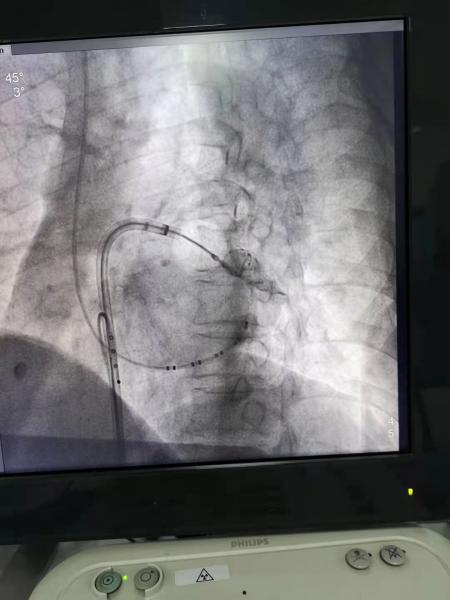

湘西州人民医院心内二科团队在手术室行心房颤动冷冻球囊消融术。

手术现场。

手术辅助仪器显示情况。